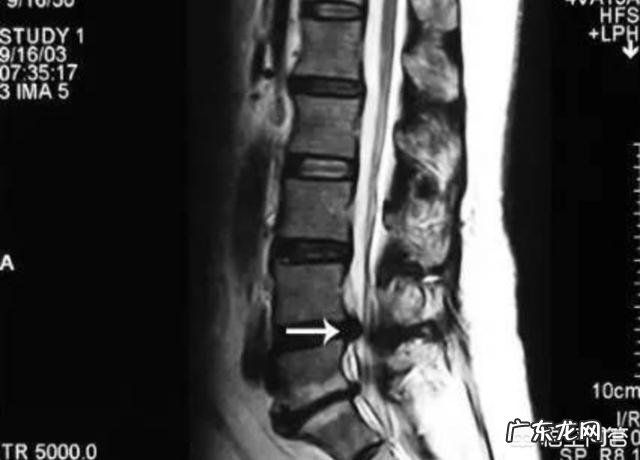

目前小关节紊乱,可以通过手的触诊判定是否有错位,X线、CT及核磁共振都是不报告的,这也是为什么很多人去医院看病,被误诊成腰椎间盘突出症、腰肌劳损或腰没毛病!